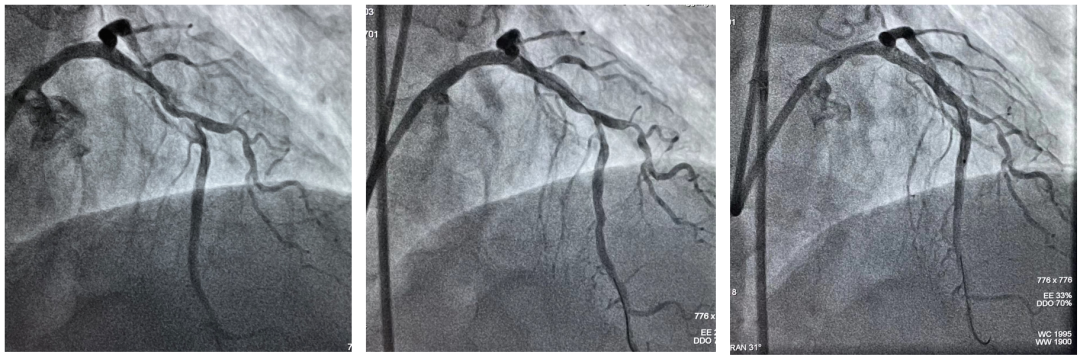

Shockwave球囊冲击波治疗冠状动脉钙化病灶前后造影及支架植入术后造影

延长导管支持下,3.0mmx12mm Shockwave冲击波球囊精准定位于前降支近段钙化最重处,先后触发60次脉冲冲击波(6个周期),实施钙化斑块碎裂术,对治疗段进行低压球囊扩张成形,随后通过OCT及冠脉造影融合技术证实,部分钙化病变得到松解,但中段成角病变处OCT提示仍有严重偏心钙化斑块,再次进行了20次脉冲冲击波(2个周期)治疗后,随着shockwave球囊能量的逐步释放,再次复查OCT显示原钙化环断裂,深层钙化碎裂。经过充分的冲击波球囊预处理,顺利完成进一步介入治疗。用时约40分钟,在患者无明显不适的情况下顺利完成介入治疗。术后患者顺利转入病房,并计划于近日出院。